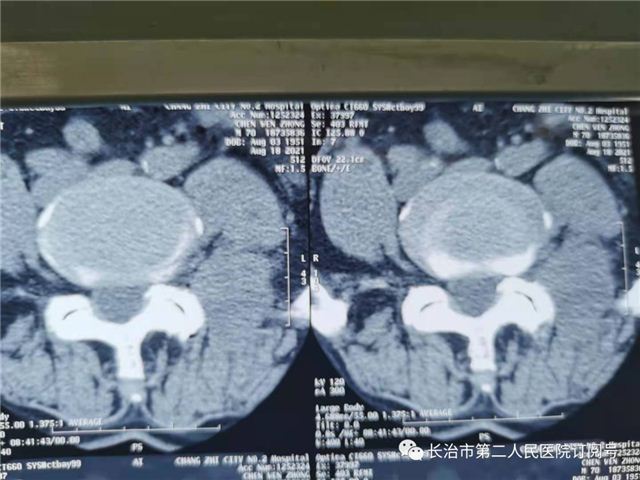

患者李某,男性,70岁,主因“腰及左下肢困痛不适5年多”。连日来的病情不断加重,腰部及左下肢疼痛难忍,入住我院,腰椎X线片检查显示:腰4/5椎体后缘自然弧线不连续呈滑脱征象,结合体格检查和影像学检查,诊断为:腰椎滑脱症、腰椎间盘突出。

术前影像